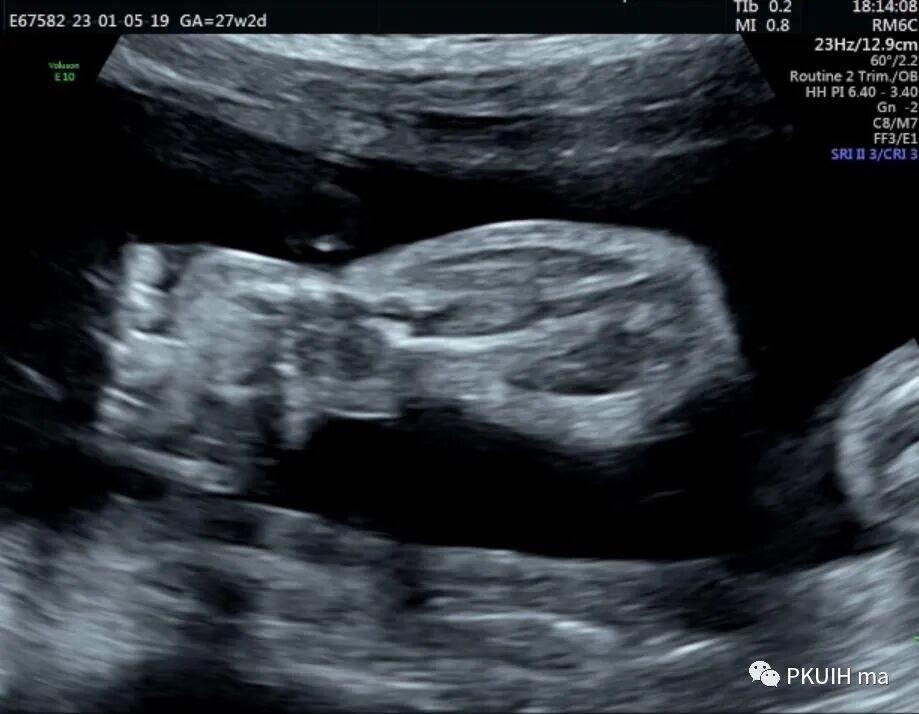

孕妇26岁,G2P0,发现胎儿肢体异常来诊,目前孕27周,超声图像如下:

四肢长骨均短缩、弯曲成角,Z值小于-4,孕妇自述第一胎也是肢体明显短,最后在当地医院引产,未做其他相关检查,本次怀孕又发现胎儿肢体短,因此来京咨询并做相关检查。